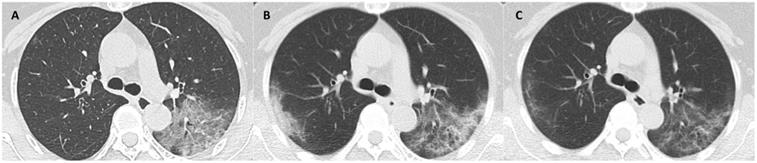

The median days of illness since symptom onset for the first, second and third milestones were 2 (range: 0-12), 10 (1-22), and 22 (7-53), respectively. The median values of total CT scores, and the mean values of each laboratory parameter at 3 milestones are listed in Table 3. Serial CT images at 3 milestones in 2 patients are shown in Figure 1-2.

Figure 1

CT scans at 3 milestones in a 65-year-old woman with COVID-19 pneumonia. (A) Initial CT obtained on illness days 1 showed ground-glass opacity in left upper lobe. (B) Worst CT obtained on illness days 8 showed ground-glass opacity and consolidation with increased extent in bilateral upper lobes. (C) CT scan before discharge obtained on illness days 18 showed substantial residual ground-glass opacity. The patient was discharged on illness days 19.